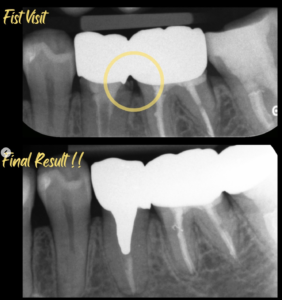

連結されたクラウンの虫歯治療をしました。クラウンの境界(マージン)が合っておらず、かなり深い虫歯になっていました。レントゲンからもわかるように、6番の歯根がかなり近接しておりますので、型取り(印象)が困難だったことが考えられます。クラウンの形態も理想的に作ることができなかったでしょう。従って、このような全く適合していない修復物が装着されてしまったと推測できました。

このような歯茎の中まで虫歯になっている場合は、修復が難しく、抜歯が第一選択になります。患者様は、抜歯するならインプラント治療を希望されました。しかし、患者様は32歳。できるなら歯を保存してインプラントの介入を遅らせたいと思いました。